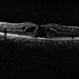

- Chloroquine maculopathy

- chloroquine maculopathy, drug toxicity

- Fundus of the left eye of a 56 year-old female with history of rheumatoid arthritis treated with chloroquine.